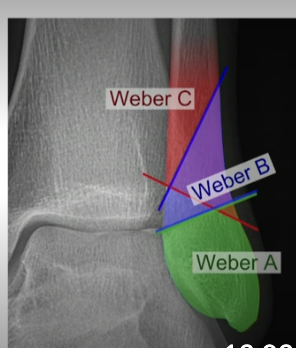

What are the Weber classification for a lateral malleolar fracture?

Weber A = stable, lower; WBAT

Weber B=higher up @ ankle joint, potentially unstable, immobilize, NWB, Urgent ortho follow up.

Weber C = higher up at ankle joint, needs surgery